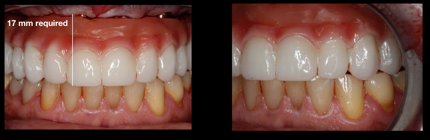

At the time of consultation, a patient requested a cosmetic makeover without endodontic therapy and traditional crown-and-bridge. After discussing removable denture options and comparing fixed implant-supported full-arch zirconia, the patient felt the best concept for achieving his goals was to accept and commit to implant-supported full-arch restoration with zirconia. The initial diagnostic work-up included intraoral scanning to provide a digital impression of the maxillary and mandibular arches, CBCT, digital bite registration, and intraoral photography. The diagnostics revealed a requirement for bone reduction to allow enough restorative space to place implants at the correct level and have enough interocclusal distance to fabricate an ideal restoration. Figure 15 depicts a computer-designed chrome 3D-printed bone-reduction guide. After bone reduction and implant placement, multi-unit abutments (MUAs) with restorative cylinders were placed within the confines of the designed chrome indexing guide to relate the PMMA provisional to the bone-reduction guide and implant osteotomy assembly. Integrating digital technology with analog dentistry generates a smooth intaglio surface during the soft-tissue healing and osseointegration phases (Figure 16). On conversion of the PMMA provisional (luting the cylinders to the PMMA prosthesis) after implant placement, torqueing of the MUAs, and providing for balanced occlusion, the occlusal scheme and the midline were established. A 17-mm interocclusal dimension from the implant platform at the incised edges of the maxillary prosthesis was required (Figure 17). The central and lateral views showed a characterized PMMA that was acceptable to the patient in the esthetic zone. The flanges of the PMMA provisional were low-profile and created a ridge lap pontic throughout the restoration. The hygiene requirements for this provisional were light brushing and rinsing. Oral hygiene care with a water pick may begin 8 weeks after initial implant placement, after the integration and soft tissue have been completed.

Fig 15. Bone-reduction guide; note the pink collar visible in the

right-hand image.

Figure 15

Fig 17. PMMA provisional, central and lateral views.

Figure 17